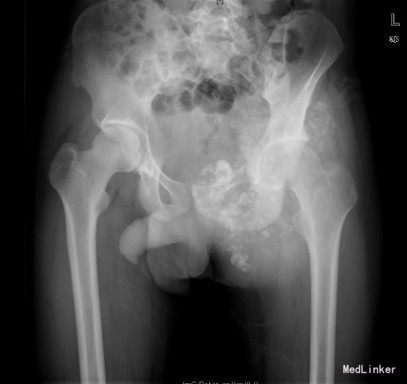

患者男,22岁,因“左臀部包块伴疼痛,进行性增大8+月”入院。入院前8+月,患者无明显诱因出现左臀部疼痛,并发现局部有包块。疼痛为钝痛,坐时加重,常反复,不伴发热及盗汗。于当地医院就诊,怀疑骨盆肿瘤;现为求进一步诊疗来我院就诊。

查体:左侧臀部内侧区隆起,局部皮肤无充血红肿,无浅静脉怒张,无皮肤破溃、皮疹及足癣。左侧臀部内侧区及左侧腹股沟区可触及巨大圆形包块,质硬,压痛明显,皮温不高,无明显触觉减退区,左足背动脉搏动正常,肢端末梢血循环正常。 辅查:骨盆CT提示左髂骨恶性肿瘤,突破皮质,边界不清,部分钙化。

初步诊断:左侧骨盆骨肉瘤(Ⅰ+Ⅱ+Ⅲ区) 诊疗计划:完善术前抽血常规、心电图及胸片等检查后择期手术治疗。